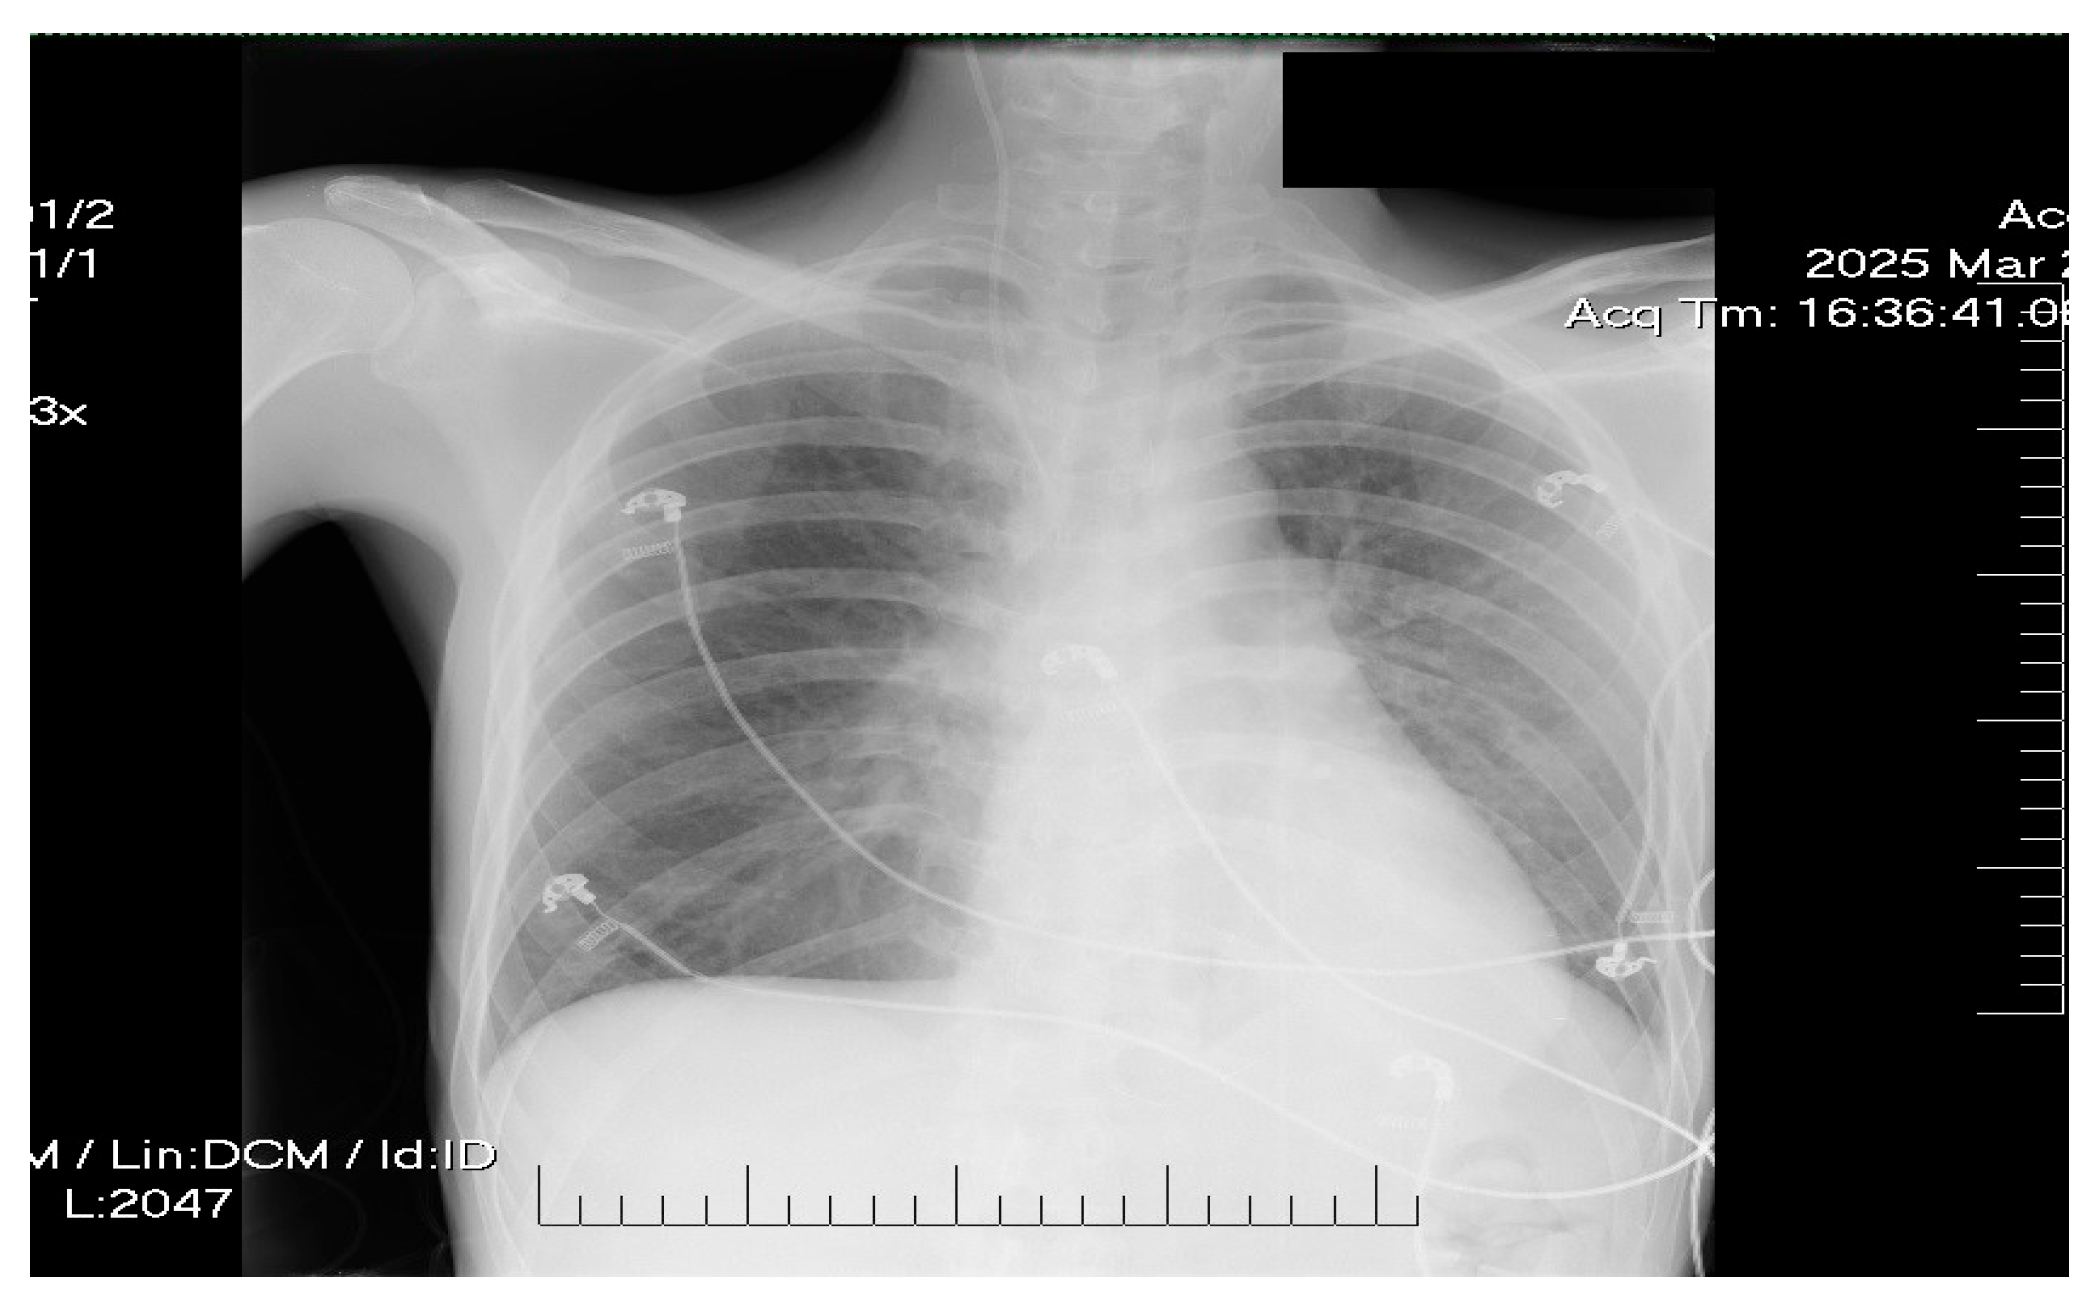

2. Case Presentation